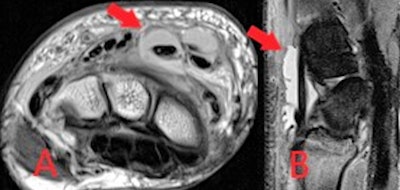

The MRI sequences employed in suspected soft tissue infection typically include T2, a fluid-sensitive sequence such as short-tau inversion recovery (STIR), and unenhanced and postcontrast T1. Diffusion-weighted imaging (DWI) may be added in certain cases, such as to assess for abscess formation, and fat-saturated T2 or enhanced T1 sequences can be used to improve the delineation of inflammation, Delaney and colleagues continued.

A gradient echo sequence may be added in more severe cases with suspected hemorrhage or necrotizing fasciitis. In cellulitis, high T2 and STIR signal intensity with corresponding T1 signal intensity of the subcutaneous tissues with overlying skin thickening is seen, and there is enhancement following gadolinium administration.

"MRI provides the most accurate evaluation of the extent of deeper infections and of surrounding soft tissue anatomy and can also assess for associated abnormality of adjacent bones or joints," they wrote. "On MRI, soft tissue abscesses demonstrate internal high T2 and STIR signal with corresponding low T1 signal, peripherally enhancement following intravenous gadolinium administration and restrict diffusion on DWI."